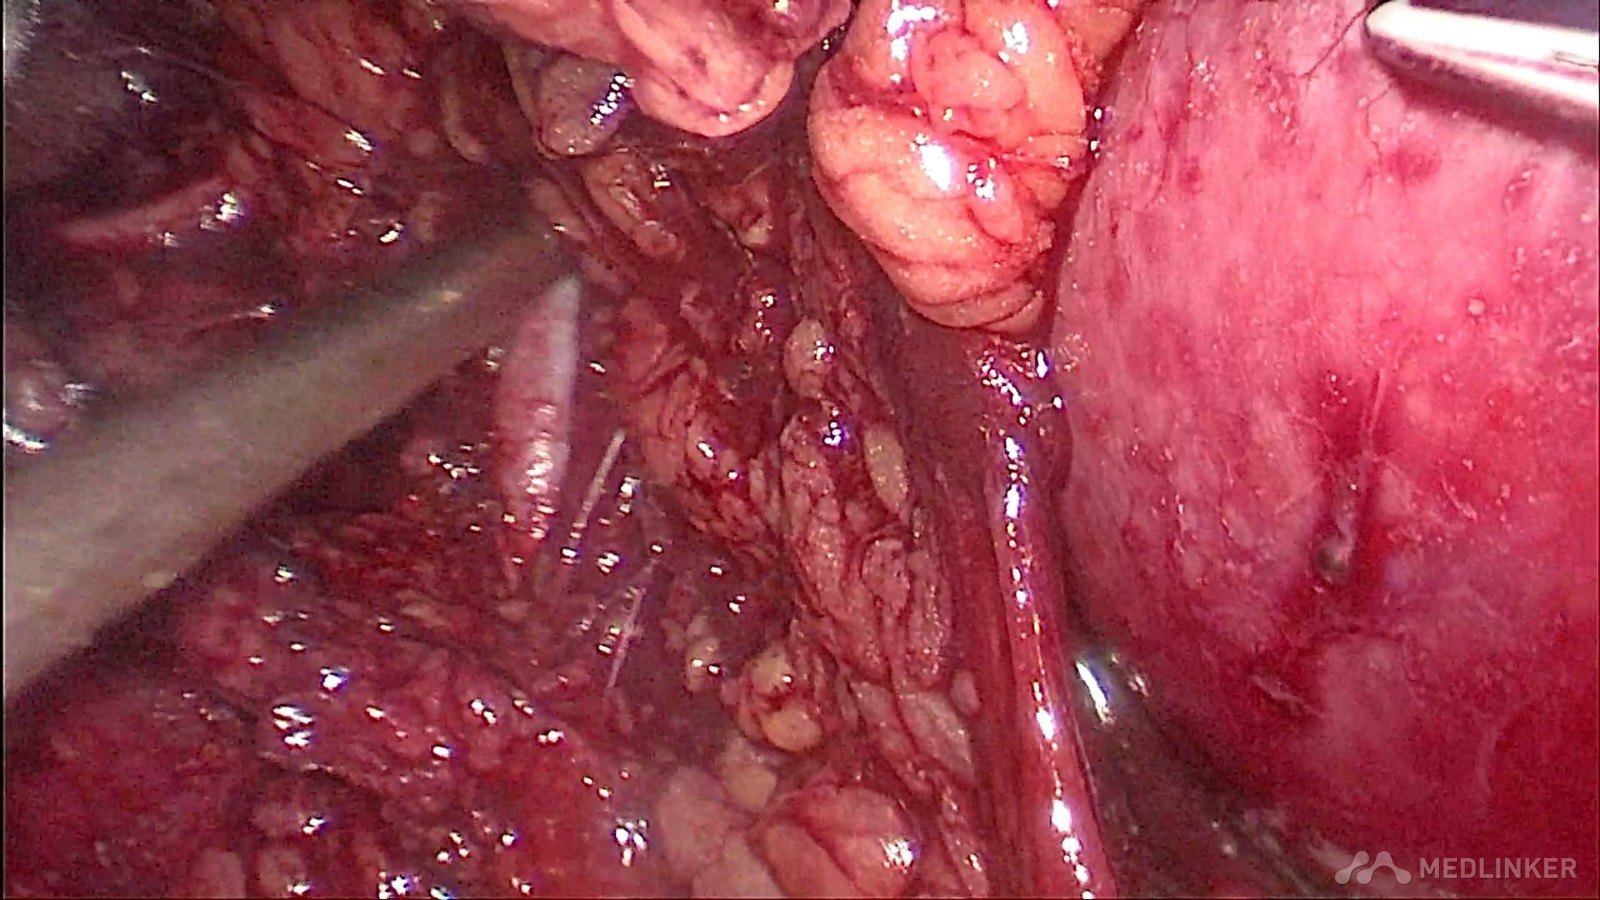

夹闭肾段动脉,防止出血,并电凝肿瘤切面减少切缘阳性率的发生

可吸收线连续缝合残留肾脏创面,减少出血,促进肾功能的保护

缝合完毕后,开放右肾动脉,仔细检查创面渗血情况和缝合张力,必要时可加针缝合减少渗血